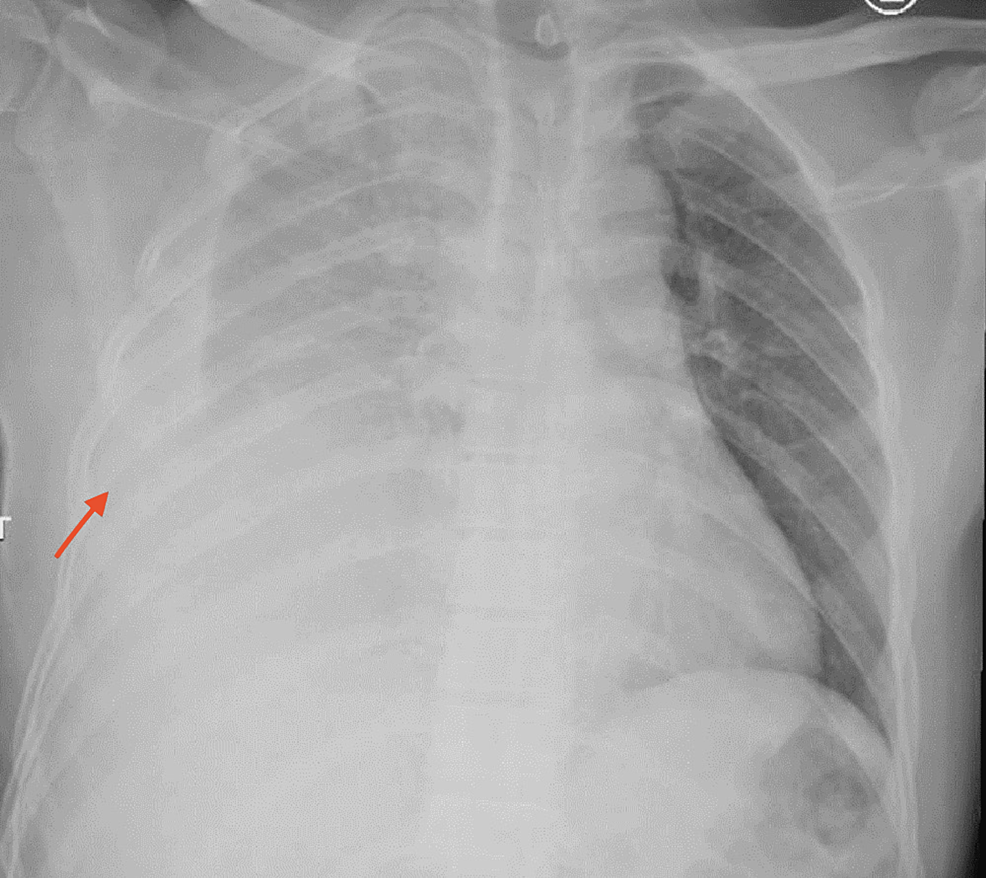

Chest radiograph showed the left side hemothorax Download Scientific How To Identify Hemothorax On Chest X Ray Most often results from trauma to intrathoracic structures. In the normal unscarred pleural space, a hemothorax is noted as a meniscus of fluid blunting the costophrenic angle or diaphragmatic surface and. Hemothorax is blood in the pleural cavity. A chest ct or further testing may then be considered. Exact distinction between a “bloody pleural effusion” and a hemothorax is. When. How To Identify Hemothorax On Chest X Ray.

Hemothorax is blood in the pleural cavity. Most often results from trauma to intrathoracic structures. Exact distinction between a “bloody pleural effusion” and a hemothorax is. In the normal unscarred pleural space, a hemothorax is noted as a meniscus of fluid blunting the costophrenic angle or diaphragmatic surface and. When a chest tube is placed, the fluid may be evaluated to. A chest ct or further testing may then be considered.